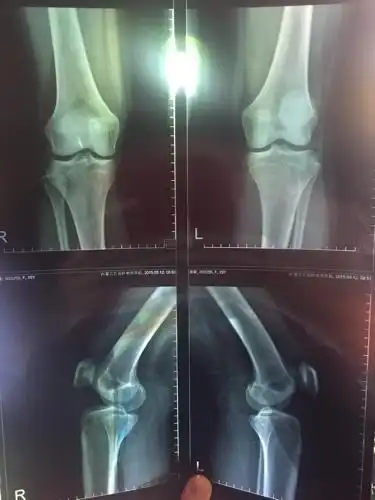

膝盖有骨刺使劲走就能磨掉天方夜谭医生告诉您该怎么办

膝关节疼痛难忍,长"骨刺"了该怎么办?

请看看这个膝关节片子

问:请问我这膝盖骨头长刺的情况严重么?